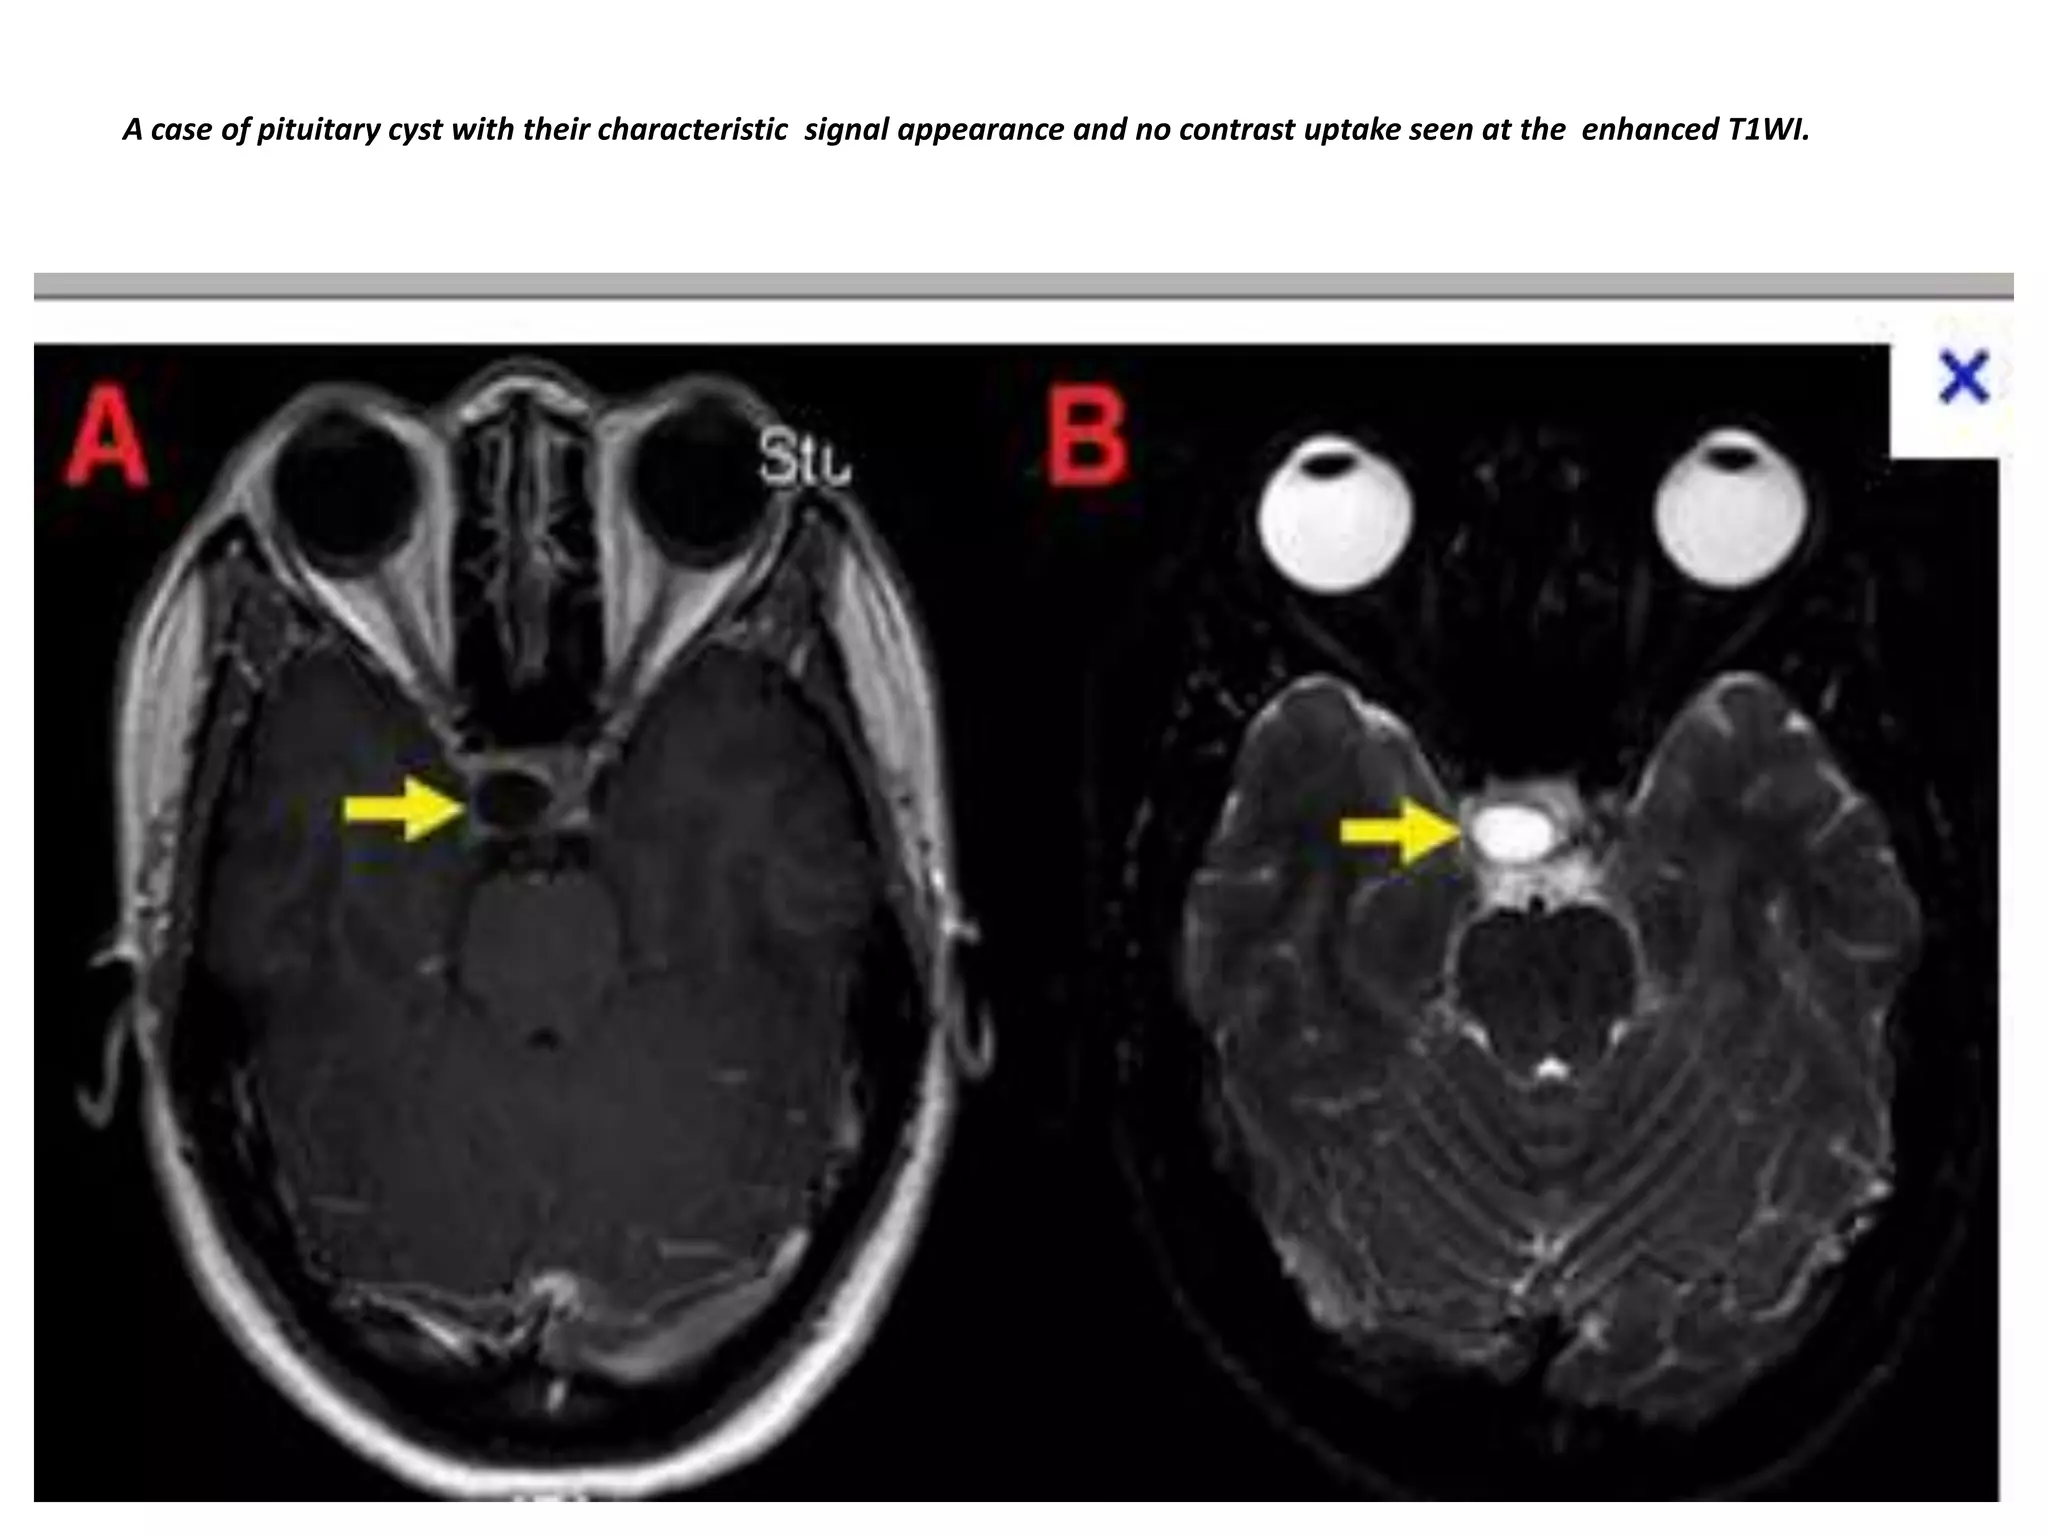

Cystic rounded lesion within the gland which appears of low signal at the T1WI and of bright

signal at the T2WI. No contrast uptake within the lesion at the enhanced study, related to cystic

microadenoma. The stalk is deviated to the right side.

A case of pituitary cyst with their characteristic signal appearance and no contrast uptake seen at the enhanced T1WI.